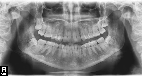

Недавно задумалась об установке брекет-системы, выбрала клинику, сходила на консультацию. Врач сказала, что у меня большая скученность зубов, зубы неправильно смыкаются, вследствие чего могут быть в будущем проблемы с челюстями, так же развивается пародонтоз из-за кривого развития зубов. Врач посоветовала мне самолигирующиеся брекеты, но они мне не по карману, я рассчитывала ставить обычные керамические брекеты. Скажите, если пациент выбирает брекет-систему, исходя из своих финансовых возможностей, то любая, выбранная система будет положительна для лечения прикуса?

Уважаемая Ирина, пациент не выбирает брекет-систему и не ставит диагнозы. Но в вашем случае можно абсолютно спокойно установить керамические системы, отличаются они от самолигирующих только тем, что обычные лигатурные керамические будут регулироваться на приеме у врача раз в две недели.